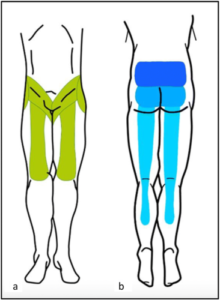

Radiation Pattern of the Pain

While lumbar facet joint pain typically starts in the lower back, it can also radiate to other areas of the body. The radiation pattern of this pain is often more localized than the radiating pain associated with conditions like sciatica. It commonly spreads to the buttocks, thighs, and sometimes the groin. This radiation is usually limited to the same side as the affected facet joint.

Illustration of distribution pattern related to facet joint pain.